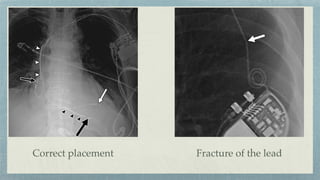

Cardiac Pacemaker

Single lead- RV

Double leads- RV + RA

Triple leads- RV+ RA+ LV

Fracture of the lead

Correct placement

Tip displaced slightly downwards